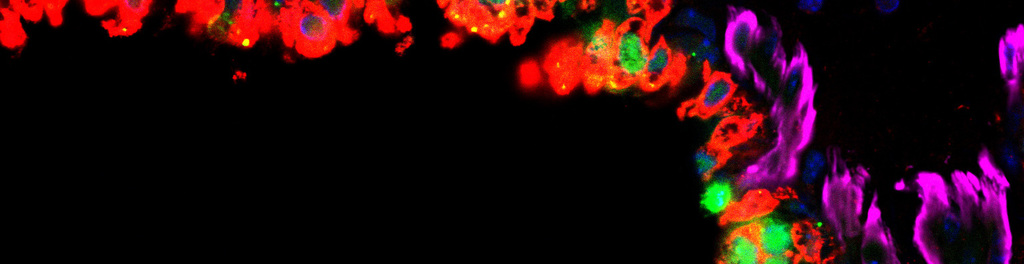

Tradewind has developed a multifaceted attack antibody for ovarian cancer. This antibody drug attacks primary and disseminated cancer cells directly. It also blocks the activity of immune cells called myeloid-derived suppressor cells (MDSCs). MDSCs potently suppress the activity of CD4+ and CD8+ T cells. Our antibody restores T cell anti-cancer immunity to enable and expand the utility of checkpoint inhibitors. It has been validated in vivo.